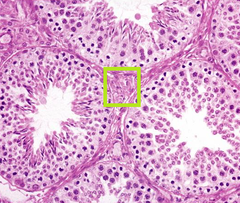

Normal seminiferous tubules Spermatogonia (near basal lamina) Spermatids (thin near lumen) Leydig cells

Front

What is this? Name the three main cells that you can see

Back

Leydig cells (interstitial cells)

whats in the box

Intratubular multinucleated cell Testicular Degeneration/atrophy

This is a seminiferous tubule. What is the red arrow? What does that indicate

testicular degeneration Spermatids are missing Multinucleated cells in the lumen

what is this? what cells are missing? what cells are in the lumen